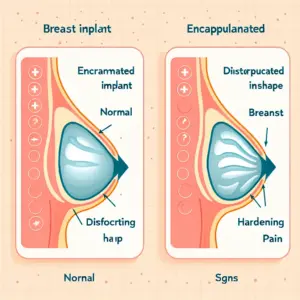

A melhor cirurgia para levantar as mamas varia conforme o grau de ptose, volume e pele, com técnicas específicas para cada caso. Avaliação médica personalizada é essencial para resultados naturais e satisfatórios.